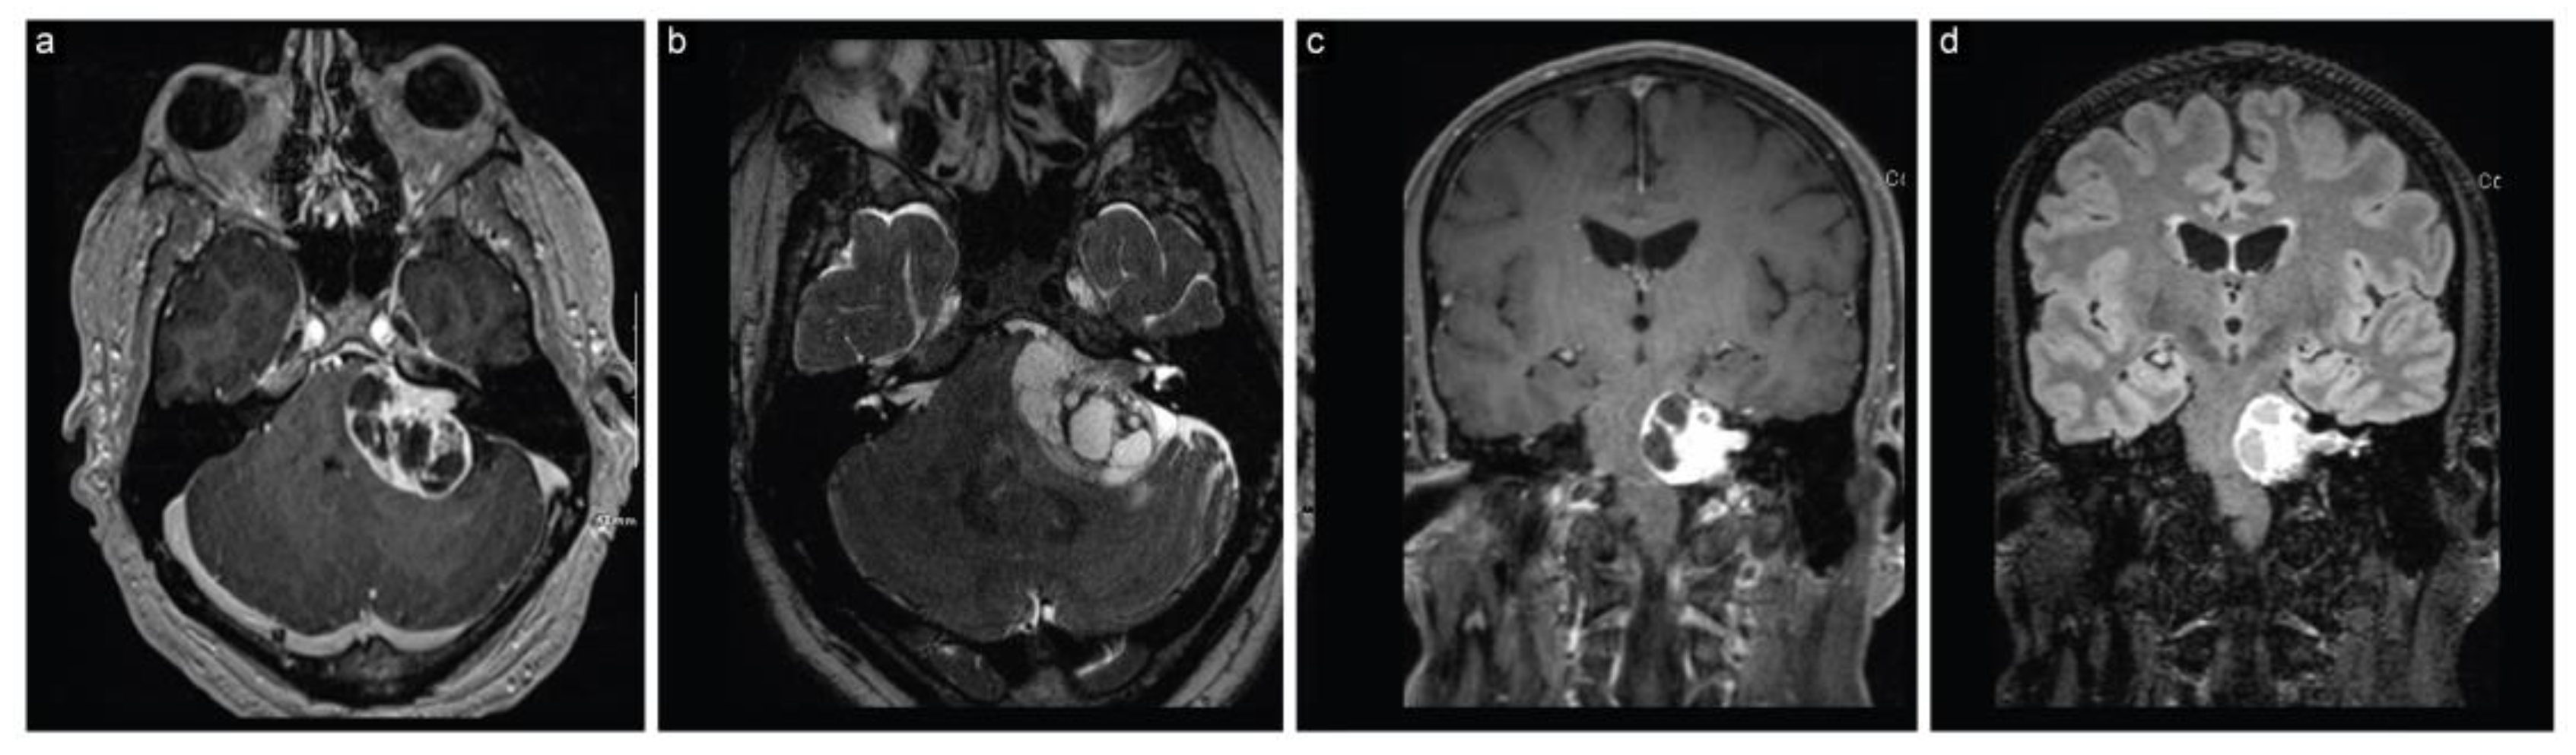

Postoperative examinations revealed House–Brackmann grade 1 facial nerve function and an early postoperative MRI confirmed the gross total resection of the tumor (Figure 6). The patient remained tumor-free with normal facial nerve function at the 1-year follow-up.

Figure 6.

Case 2 post-stage 2 neuroimaging findings. (a) Axial T1-weighted postcontrast, (b) axial T2-weighted, (c) axial FIESTA, and (d) coronal T1-weighted postcontrast MRI scans show gross total resection with decompression of the brainstem and surrounding structures.